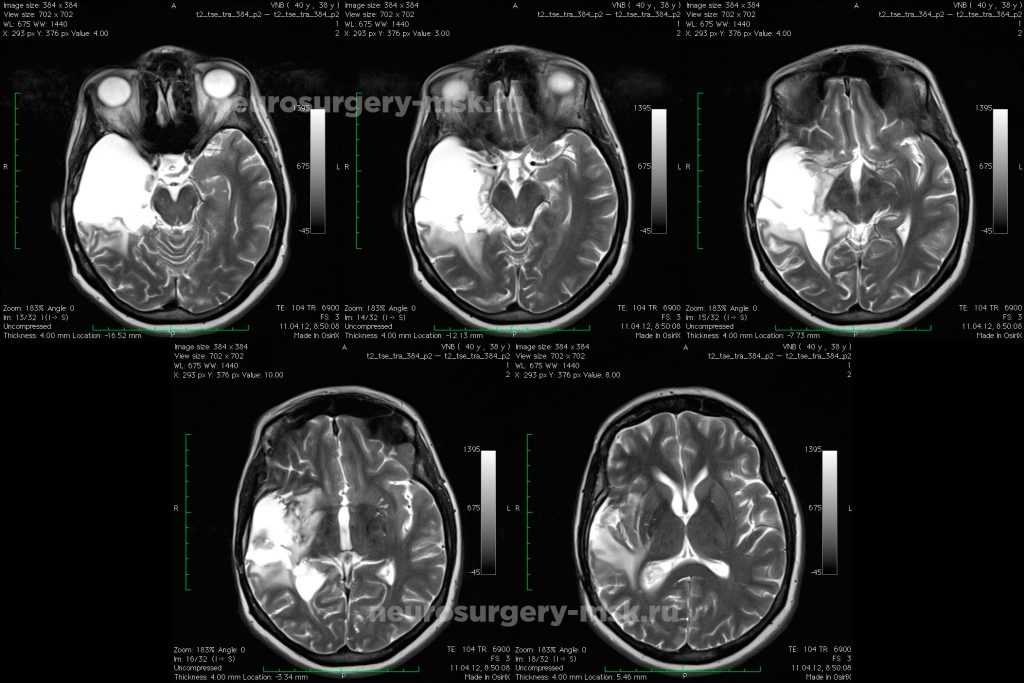

При динамическом анализе на серии наблюдений за опухолью с двусторонним поражением таламусов и моста мозга очевидно увеличение размеров образований, а так же развитие заместительной гидроцефалии на фоне атрофии мозгового вещества в силу опухолевой прогрессии и последствий лечения (рис.186).